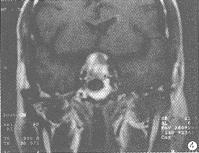

MRI信号特征:9例HPA瘤体在T1WI和T2WI均呈高信号。在T1WI上,6例呈均匀一致的高信号(图1),其余3例呈不均匀的高信号。1例表现散在点状高信号,1例瘤体中心高信号(图2),1例瘤体上半部分高信号,下半部分等信号(图3),。1例EHF引起的垂体出血在T1WI和T2WI呈不均匀的高信号,Gd-DTPA后见血肿轮廓明显强化,肿胀垂体实质略有不均匀强化(图4)。1个月后复查,肿大垂体已明显缩小,大小0.6cm,信号均匀(图5)。

图4 男,44岁。抗EHF1:320,T1WI冠状位,静脉注射Gd-DTPA后

血肿轮廓明显强化,肿胀垂体实质不均匀强化